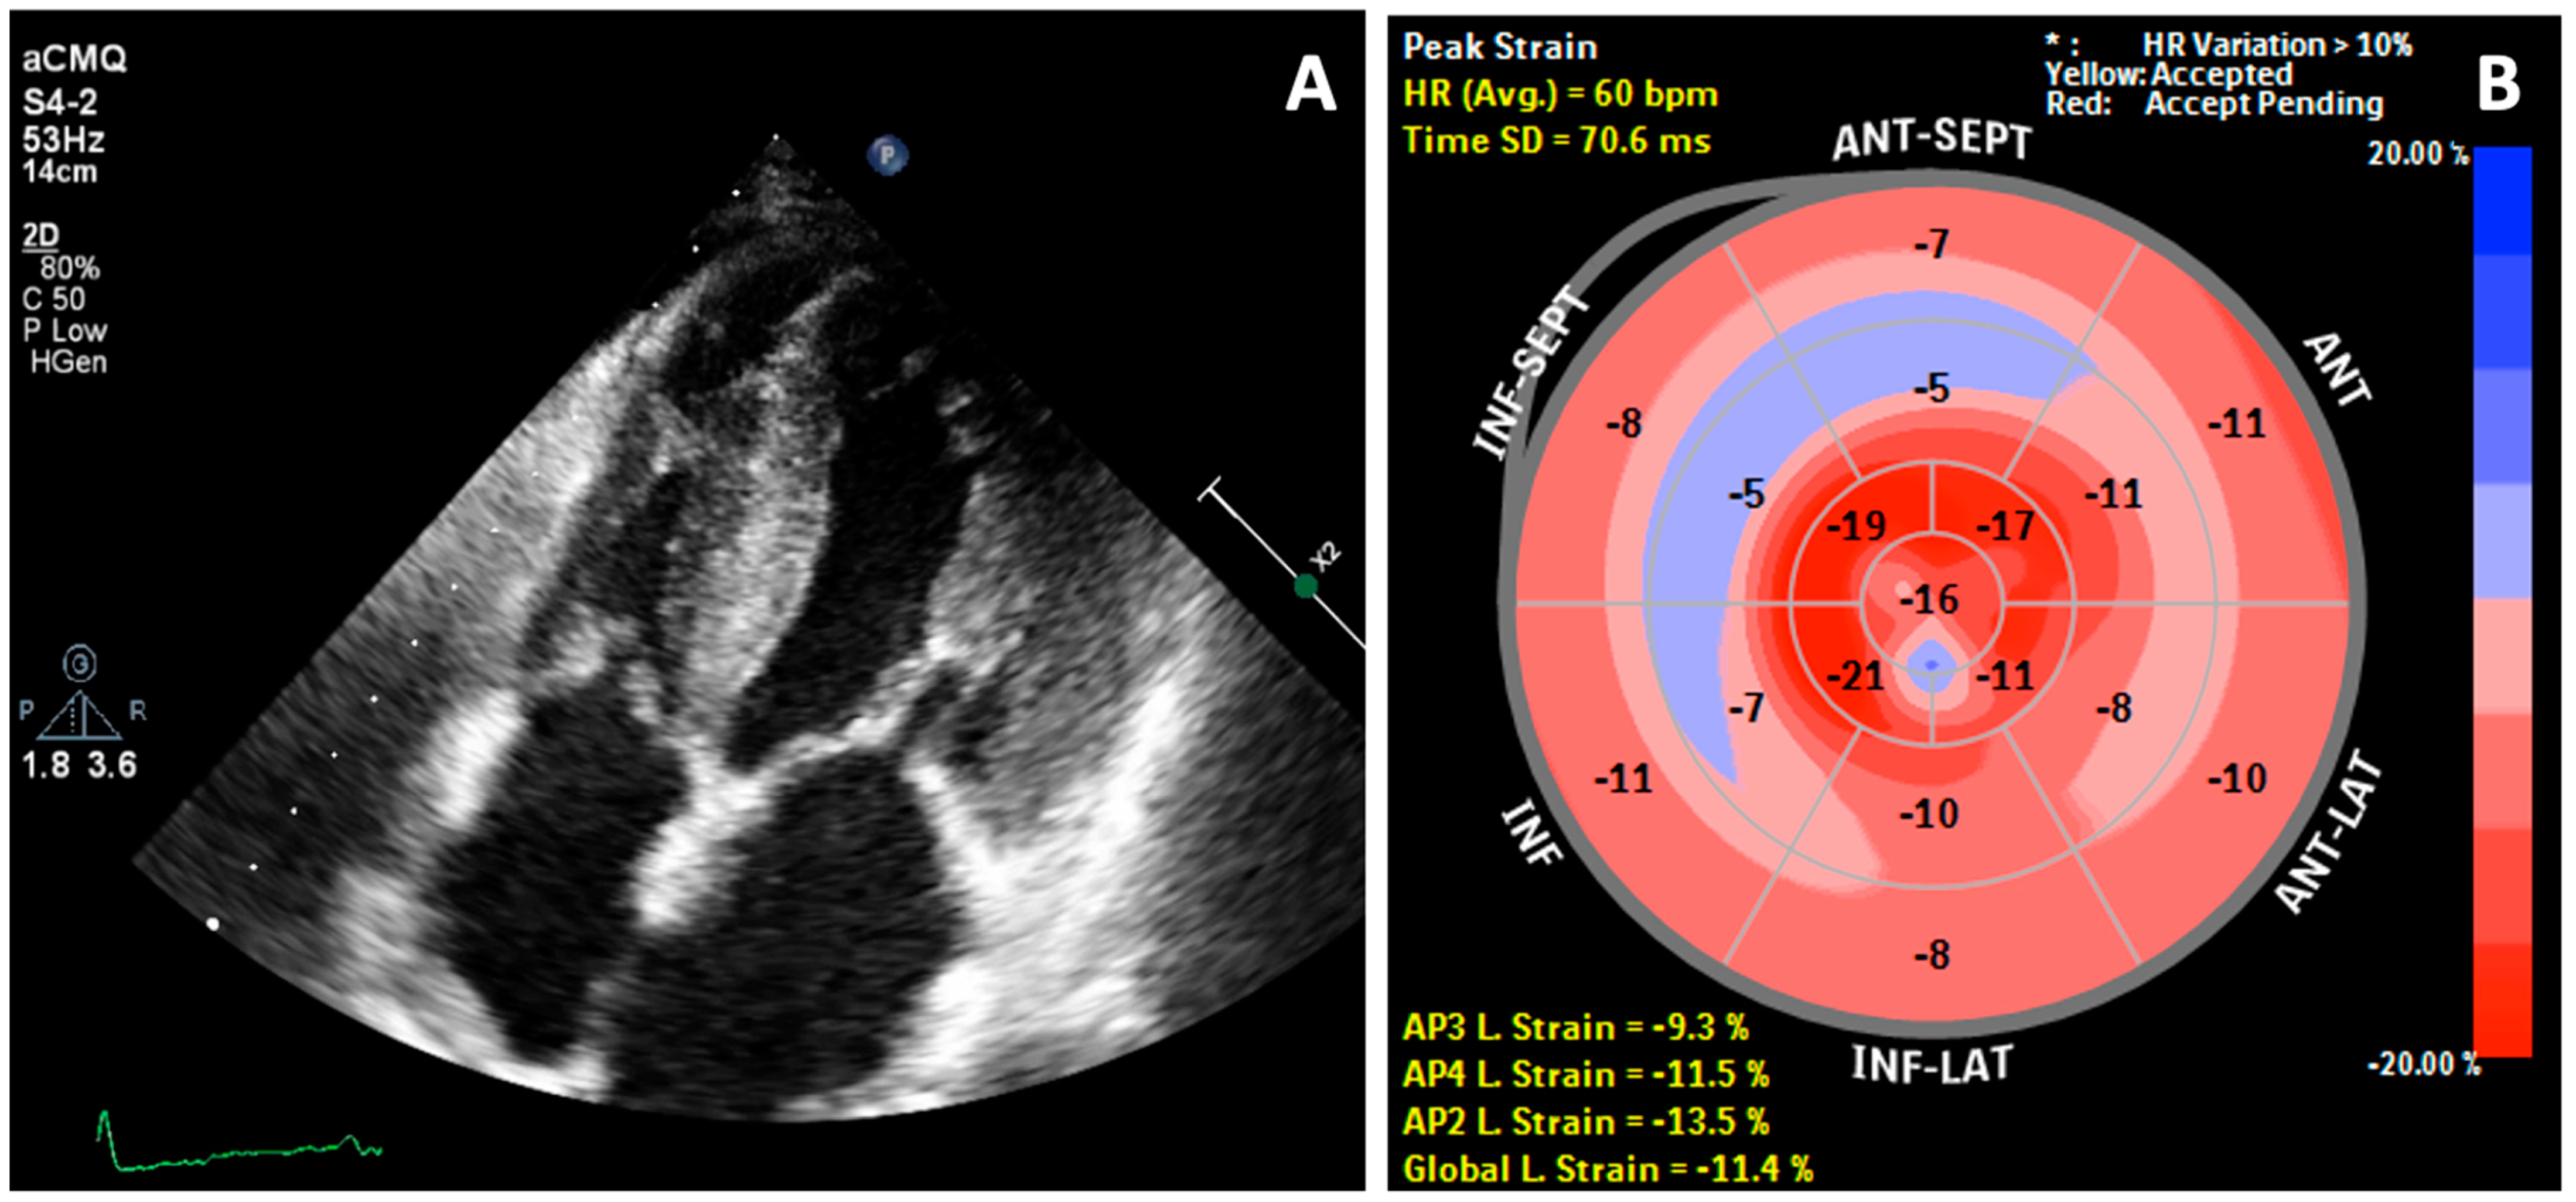

2. Case Report